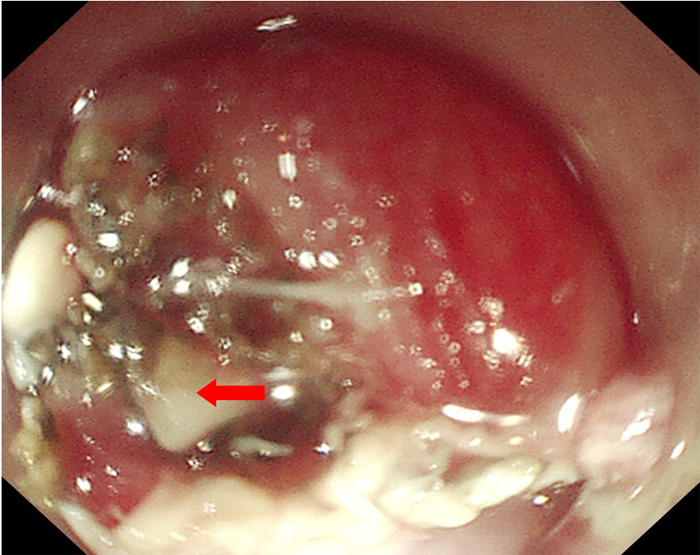

為了解魚(yú)刺與周圍的關(guān)系及是否刺入血管,患者入院后給予完善胸部強(qiáng)化CT,示胸上段管腔內(nèi)高密度影,考慮食管異物。李曙暉主任醫(yī)師結(jié)合患者病史、2次胃鏡結(jié)果及胸部CT等,分析認(rèn)為魚(yú)刺已深深扎入食管壁內(nèi),可行食管黏膜剝離術(shù)暴露出異物后再行取出。12月28日,李曙暉主任醫(yī)師在麻醉和護(hù)理團(tuán)隊(duì)的配合下行胃鏡檢查,內(nèi)鏡下距門齒18cm可見(jiàn)食管黏膜充血水腫,未見(jiàn)異物,遂用黏膜切開(kāi)刀切開(kāi)周圍黏膜及肌層,暴露出異物頂端,再用鱷口鉗鉗住魚(yú)刺頂端,順利取出一枚長(zhǎng)3cm多的魚(yú)刺,看到大部分魚(yú)刺扎入食管壁。術(shù)后對(duì)癥治療后,患者現(xiàn)已痊愈出院。

食管黏膜及肌層剝離后看到露出的魚(yú)刺